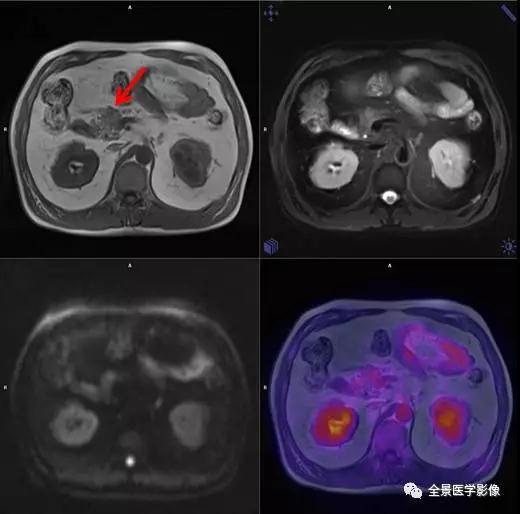

胰腺

神经内分泌肿瘤

◆ 案例:中年男性,无症状体检,检查发现胰头部小结节,病灶直径小于 1 cm,FDG 无代谢,手术病理早期神经内分泌肿瘤。

点评:

胰腺神经内分泌肿瘤较为少见,如为无功能性的通常没有症状,只能通过影像学检查发现。如果发现较晚,就会扩大手术范围,甚至引起远处转移,因此早期发现,早期处理尤为重要。

实性假乳头状瘤

◆ 案例:青年女性,胰尾部一边界清楚、类圆形异常信号灶,长径约 1.3 cm,FDG 摄取不明显,诊断为「实性假乳头状瘤」。

胰腺实性假乳头状瘤 (SPTP) 是一种罕见的良性或低度恶性的胰腺肿瘤。手术切除是该病首选治疗方法 ,肿瘤完整切除后预后良好。因为 SPTP 中有部分为低度恶性,故本病的治疗及预防的关键也是早期发现,予手术切除。

导管内乳头状黏液肿瘤

◆ 案例:老年女性,主胰管全程轻度扩张,胰体背侧紧贴胰管囊性信号灶,FDG 未见明显摄取,诊断为「导管内乳头状黏液性肿瘤」。

导管内乳头状黏液肿瘤 (IPMN) 是一种较少见的胰腺囊性肿瘤。好发于老年人,最多见于 60-70 岁 。对于单发于胰腺钩突的分支型 IPMN,且直径<2.5 cm,临床可密切观察,而对于其他类型因具有潜在恶性的特征,应积极手术切除。